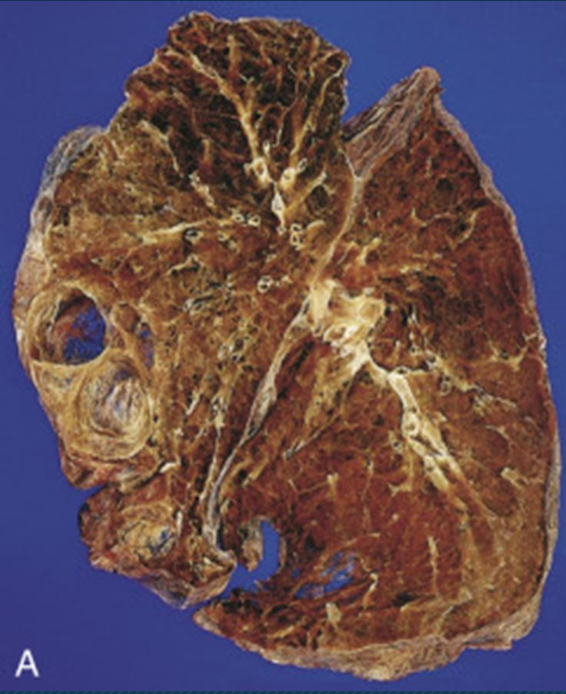

¿Cómo se ve morfológicamente las bronquiectasias?

Vias aéreas dilatadas de aspecto quístico llenos de secreción purulenta, afectación bilateral

¿Qué es?

Bronquiectasias